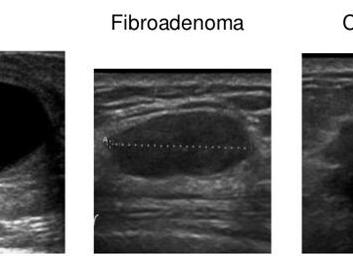

При изучении результатов исследования, врач должен поставить точный диагноз. Схожее описание клинической картины имеют узелки и опухоли фиброзного или фиброзно-кистозного типа. Это могут быть фиброаденомы, маститы и мастиопатия.

Мастиопатия — доброкачественное образование, при пальпации которого отмечается эластичность. Киста, в отличие от рака, имеет повышенную подвижность и четкие контуры. Фиброаденома обычно обнаруживается у юных девушек, обладает гладкой поверхностью с повышенной плотностью и подвижностью.

Фиброаденомы характеризуются гладкой поверхностью, большой подвижностью и плотностью. Чаще всего появляются они в юношеском возрасте.

- Фиброаденома. Чаще развивается в молодом возрасте. По консистенции доброкачественная опухоль плотная. Фиброаденома подвижна.

Фиброаденома